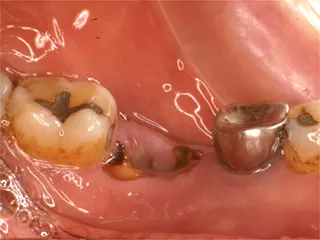

| 自費ブリッジ |

保険のブリッジ

通常のブリッジでは 正面から金属が見えてしまいますが ピンレッジでは見えません ■長所 ・金属が見えない ■短所 ・前後の歯を裏だけ削る ・前後の歯が健全な場合のみ可能 ・高い |